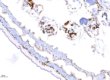

動物別:小鼠 組織臟器:胃 染色試劑套組:BioTnA, TADS03, mouse/rabbit x mouse/rabbit double stain kit ————————- 立众獨家代理的染色試劑套組,配合立众病理實驗室專業的染色技術,讓組織切片在可見光下一樣可以有清晰的雙染結果。 多重染色中相對常見的免疫螢光(IF),其操作過程相對複雜,切片保存不易,而且不易完整觀察組織形態。在可見光雙染下,上面的問題都可以獲得良好的解決!! Post navigationPreviousPrevious post:恭喜立众病理實驗室客戶的研究再次登上國際頂尖期刊!NextNext post:Safranin O stain 番紅染色Related PostsModified Movat’s Pentachrome 染色法2022-07-22Safranin O stain 番紅染色2022-02-22最佳的免疫化學染色IHC試劑套組2022-02-22可見光免疫組織化學染色雙染 Immunohistochemical double staining2022-02-22帶大家快速的認識各種切片染色技術!!2022-02-21原位雜合試驗(In situ hybridization, ISH)2022-01-14